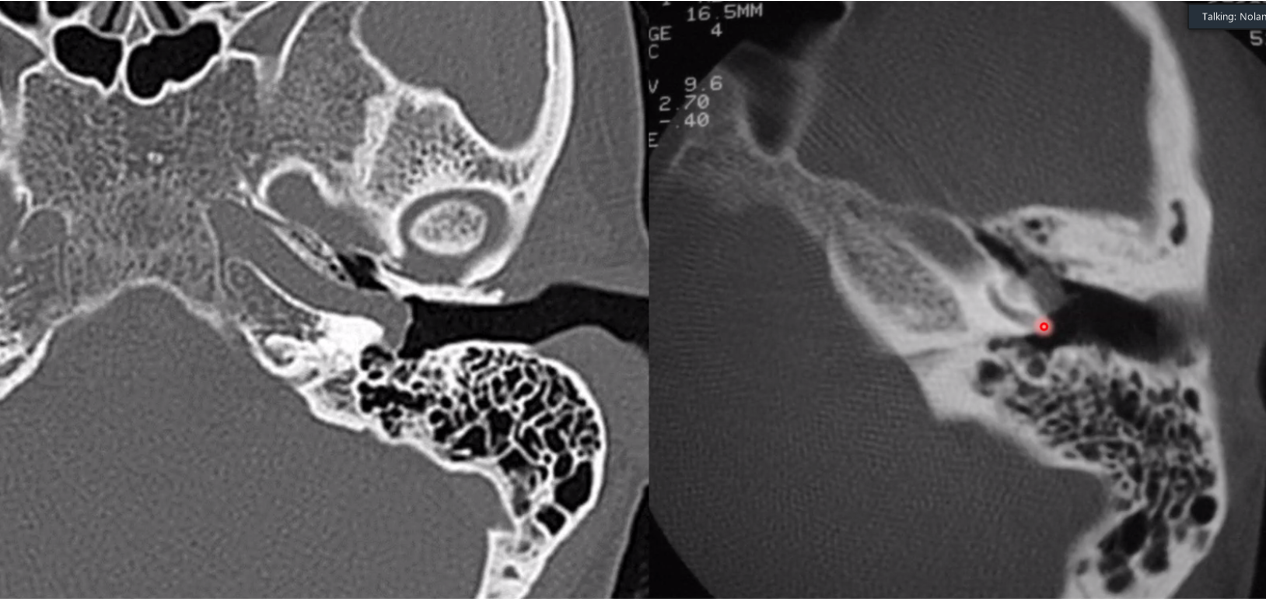

aberrant ICA

carotid > jugulare > tympanicum > vagale

what are each of these entities (they are different cases)